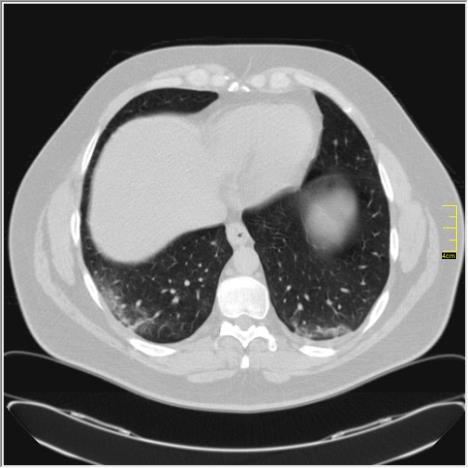

- Kod pacijenata sa "ivermektinom" postoje svi elementi kovida sa izraženom fibrozom, znači nema ni govora da neće biti komplikacija. Svi pacijenti koji koriste "ivermektin", po pravilu, nisu vakcinisani. U ovoj pandemiji je primećeno da oponenti vakcinacije pristaju na korišćenje svega drugog, pa čak i lekova za ovce, ali vakcine ne žele - napisao je dr Ivković.